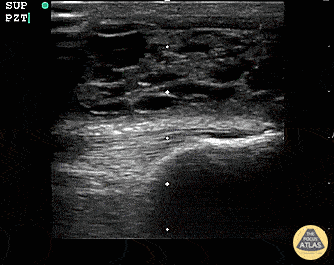

Musculoskeletal - Suprapatellar Bursitis

Suprapatellar bursitis from repetitive trauma of playing on the floor with grandchildren. Presented with over a week of knee pain and swelling. Superficial involvement and septae are possible for abscess, however it is contained within the bursal space above the patella. Arthrocentesis revealed no infection, and conservative therapy yielded improvement. Dr. Dustin Morrow